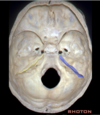

Arcuate eminence

Carotid groove of sphenoid bone

Meatal depression

Petrous temporal bone

Sigmoid sinus

Superior petrosal sinus

Tegmen

Torcula

Trigeminal prominence

Tuberculum sella

Relations of the sphenoid bone

Frontal and ethmoid anteriorly

Squamosal temporal bone laterally

Posteriorly the petrous temporal and occipital bone

What bones form the foramen lacerum?

Foramen lacerum formed by the junction of the petrous apex, sphenoid bone and occipital bone

What bounds the lateral edge of the carotid groove of the sphenoid bone?

The lingula